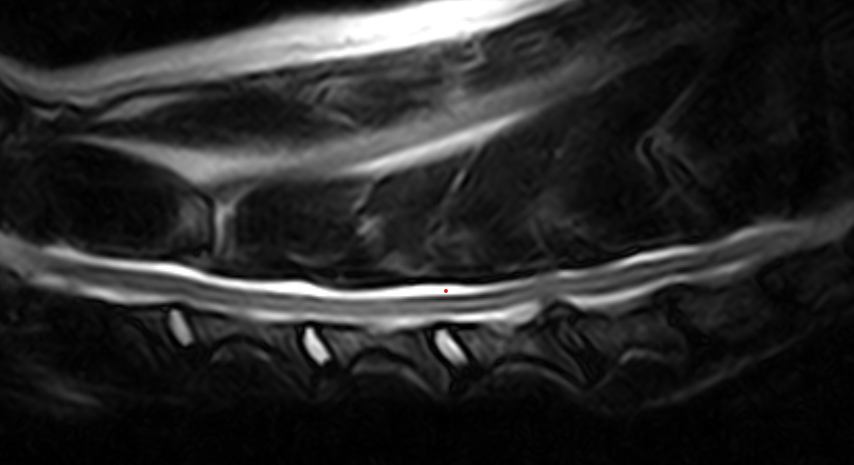

IMÁGENES CLÍNICAS

En la sección de imágenes clínicas, destacamos la precisión y claridad de nuestros estudios, respaldados por un equipo de radiólogos especializados en medicina veterinaria. Nos enorgullece ser un aliado confiable para veterinarios y clínicas, brindando un servicio rápido y eficiente para ayudar en la toma de decisiones clínicas fundamentadas.